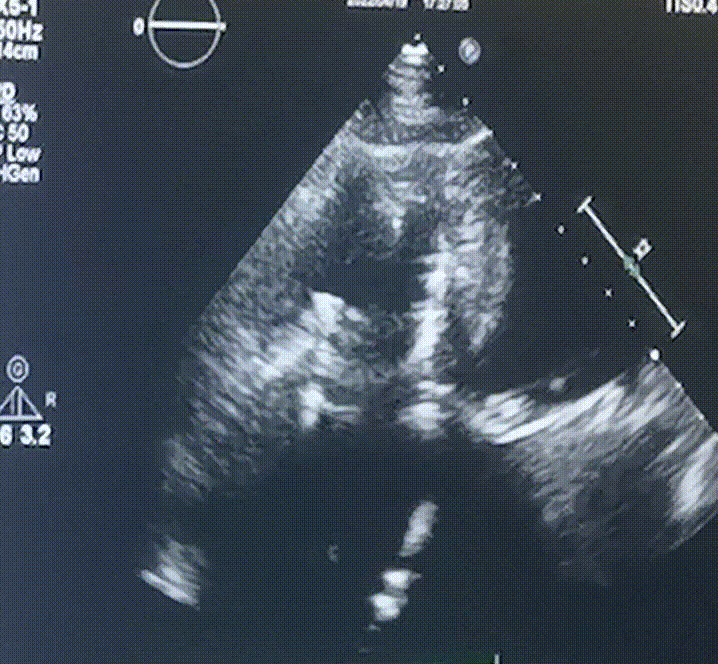

術(shù)前超聲提示:

1.右心、左房明顯增大;

2.二尖瓣人工機(jī)械瓣功能正常,無瓣周漏;

3.三尖瓣環(huán)巨大擴(kuò)張,收縮期瓣葉對合不攏,收縮期三尖瓣房側(cè)見大量反流信號,反流面積15-20cm²,TRVmax:240cm/s,跨瓣壓差:23 mmHg。

圖1.術(shù)前超聲